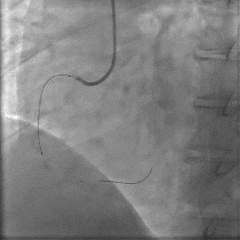

冠脉造影提示:左主干未见狭窄;左前降支近段局限性狭窄50%,中段最重狭窄40%,TIMI血流3级;回旋支无狭窄;右冠状动脉近中段可见弥漫性中度钙化,TIMI血流3级,最重狭窄70%;右冠状动脉远段TIMI血流0级,最重狭窄100%。

根据心电图及临床症状,结合冠脉造影结果考虑右冠脉为罪犯血管,决定开通右冠脉闭塞病变。

介入治疗过程:将导丝通过右冠脉中远段闭塞病变送至血管远端,送入血栓抽吸导管抽吸出红色血栓,使用球囊对病变处进行预扩张,造影示闭塞病变开通,OCT观察闭塞病变处可见红色血栓及斑块破裂,最小面积3.35mm2。后成功于病变处放置3.0×18mm药物洗脱支架一枚,造影示支架定位良好,未见明显夹层,OCT观察支架贴壁良好,支架内无血栓及夹层影,远端血流TIMI 3级,最小管腔面积5.59mm2。

冠脉造影:

介入过程: